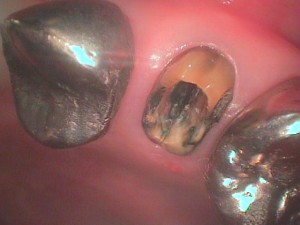

症例です。

かぶせ物がグラグラするとの事で受診されました。

土台を外すとクラックが入っていました。残念ですが抜歯の適応です。

抜歯した歯を見てみると根の先まで破折線が達していた事がわかります。